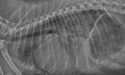

Right lateral thoracic radiograph of a small dog in ACVIM Stage C, heart failure.